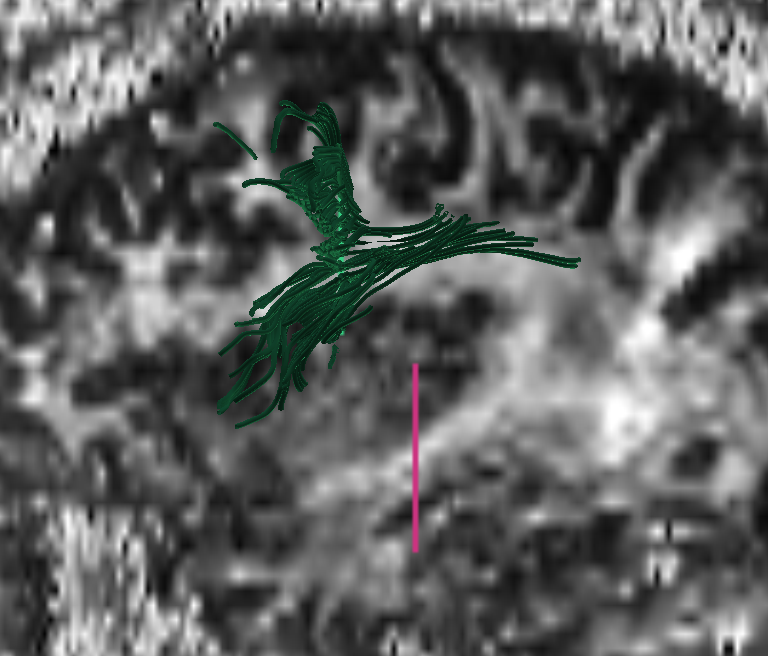

lsdi, 1.7 x 1.7 x 5 mm, coronal PA